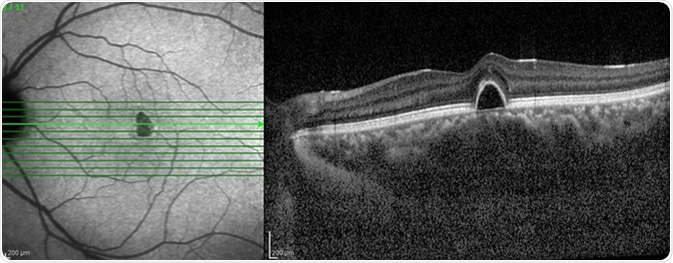

Optical Coherence Tomography (OCT) image of eye in the patient. Image Credit: Chaiwut Siriphithakwong / Shutterstock

OCT is a high-resolution optical imaging technique that can produce a cross-section image of an object. The image can be produced in real time, allowing this technique to have many applications. There are two methods of OCT: time domain and spectral domain. Within these categories, each one can be performed in different ways. Which one is used depends on the sample being investigated and the advantages and disadvantages of each method.

SD-OCT can be used to measure the thickness of the retina and to evaluate the effects of certain diseases on this tissue. The decline in visual acuity seen in diabetic macular edema is caused by retinal thickening. There are many other parameters within the retina that can be measured using OCT such as changes in drusen volume, macular holes, subretinal fluid, and pigment epithelium detachment.